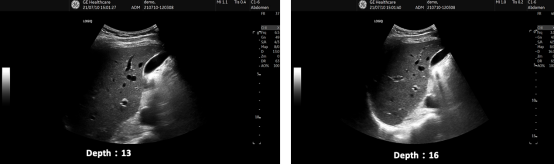

扇窗大小和深度(Scan Area/Angle、Depth) 5 E- [( o: V- K" w# {- |1 ^

图像深度设置是指在检测解剖结构时声波进入人体的深度。测量单位为cm或mm。在显示结构或血流时应最大化。但深度和扇面宽度设置可能影响帧频。由于心脏是一个快速运动的结构,高帧频可以增强瞬时分辨率。较小的扇角在某些情况下可以用来加强图像质量。  5 D6 _% g' _2 Q O% h/ C